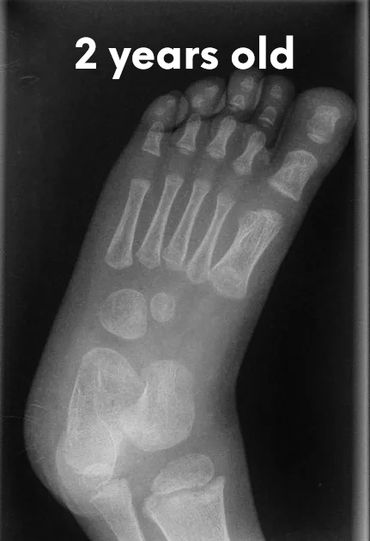

Babies’ feet are very soft and mostly made of cartilage in the first years of life. Their bones are still forming, and they have a thick layer of fat that makes their feet look chubby. This is why it’s important not to restrict their feet with tight or rigid shoes, as it could affect the natural shape and growth.

Let's check what their foot bones look like.

Pictures below will let you understand how babies' feet are developed.

Dear parents, children’s feet are developing structures, and the absence of an arch is a typical stage of development. The developing foot is not structurally ‘flat’; it is a highly compliant and plastic, that can respond to multiple factors, many of which we do not understand. Detailed X-RAY pictures above, let us understand that babies' foot bones are not connected till the teen years. Only at the age of 14, we may consider that the bones in the feet are developed and have reached their connections.

At the age of 18, we have fully completed foot structure, where muscles and bones create the whole support system.

Flat feet are a normal stage of development for children under the age of 3. The arch on the inside of the foot has not yet formed, and as children grow and walk, the soft tissues in the feet gradually tighten, shaping the arch over time. Most children have what is called a flexible flatfoot, where the arch only appears when they sit, tiptoe, or when the big toe is gently bent back.